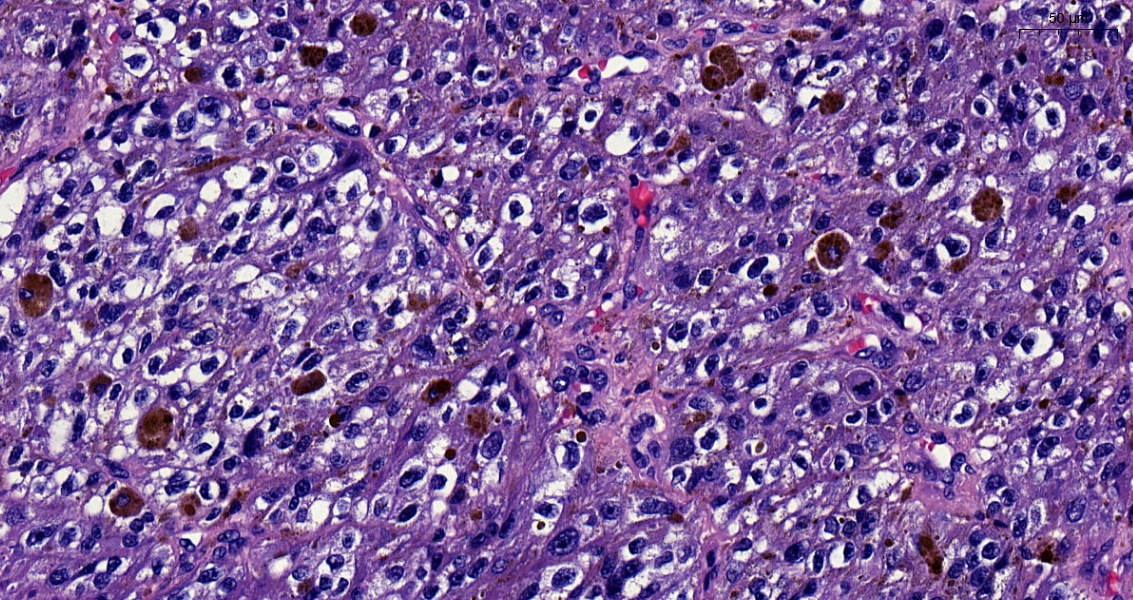

Rectal polyp. Pseudoinvasion or a pT1? A case of epithelial displacement vs pT1, before #GIpath short course at #USCAP23 What do you think?🤔

Misplaced adenoma with high-grade dysplasia? Invasive adenocarcinoma -pT1? Wouldn't you love to know what the GI pathology gurus would call this? Do come to our short course - featuring Deepa Patil and Reet Pai #USCAP23 #GIpath